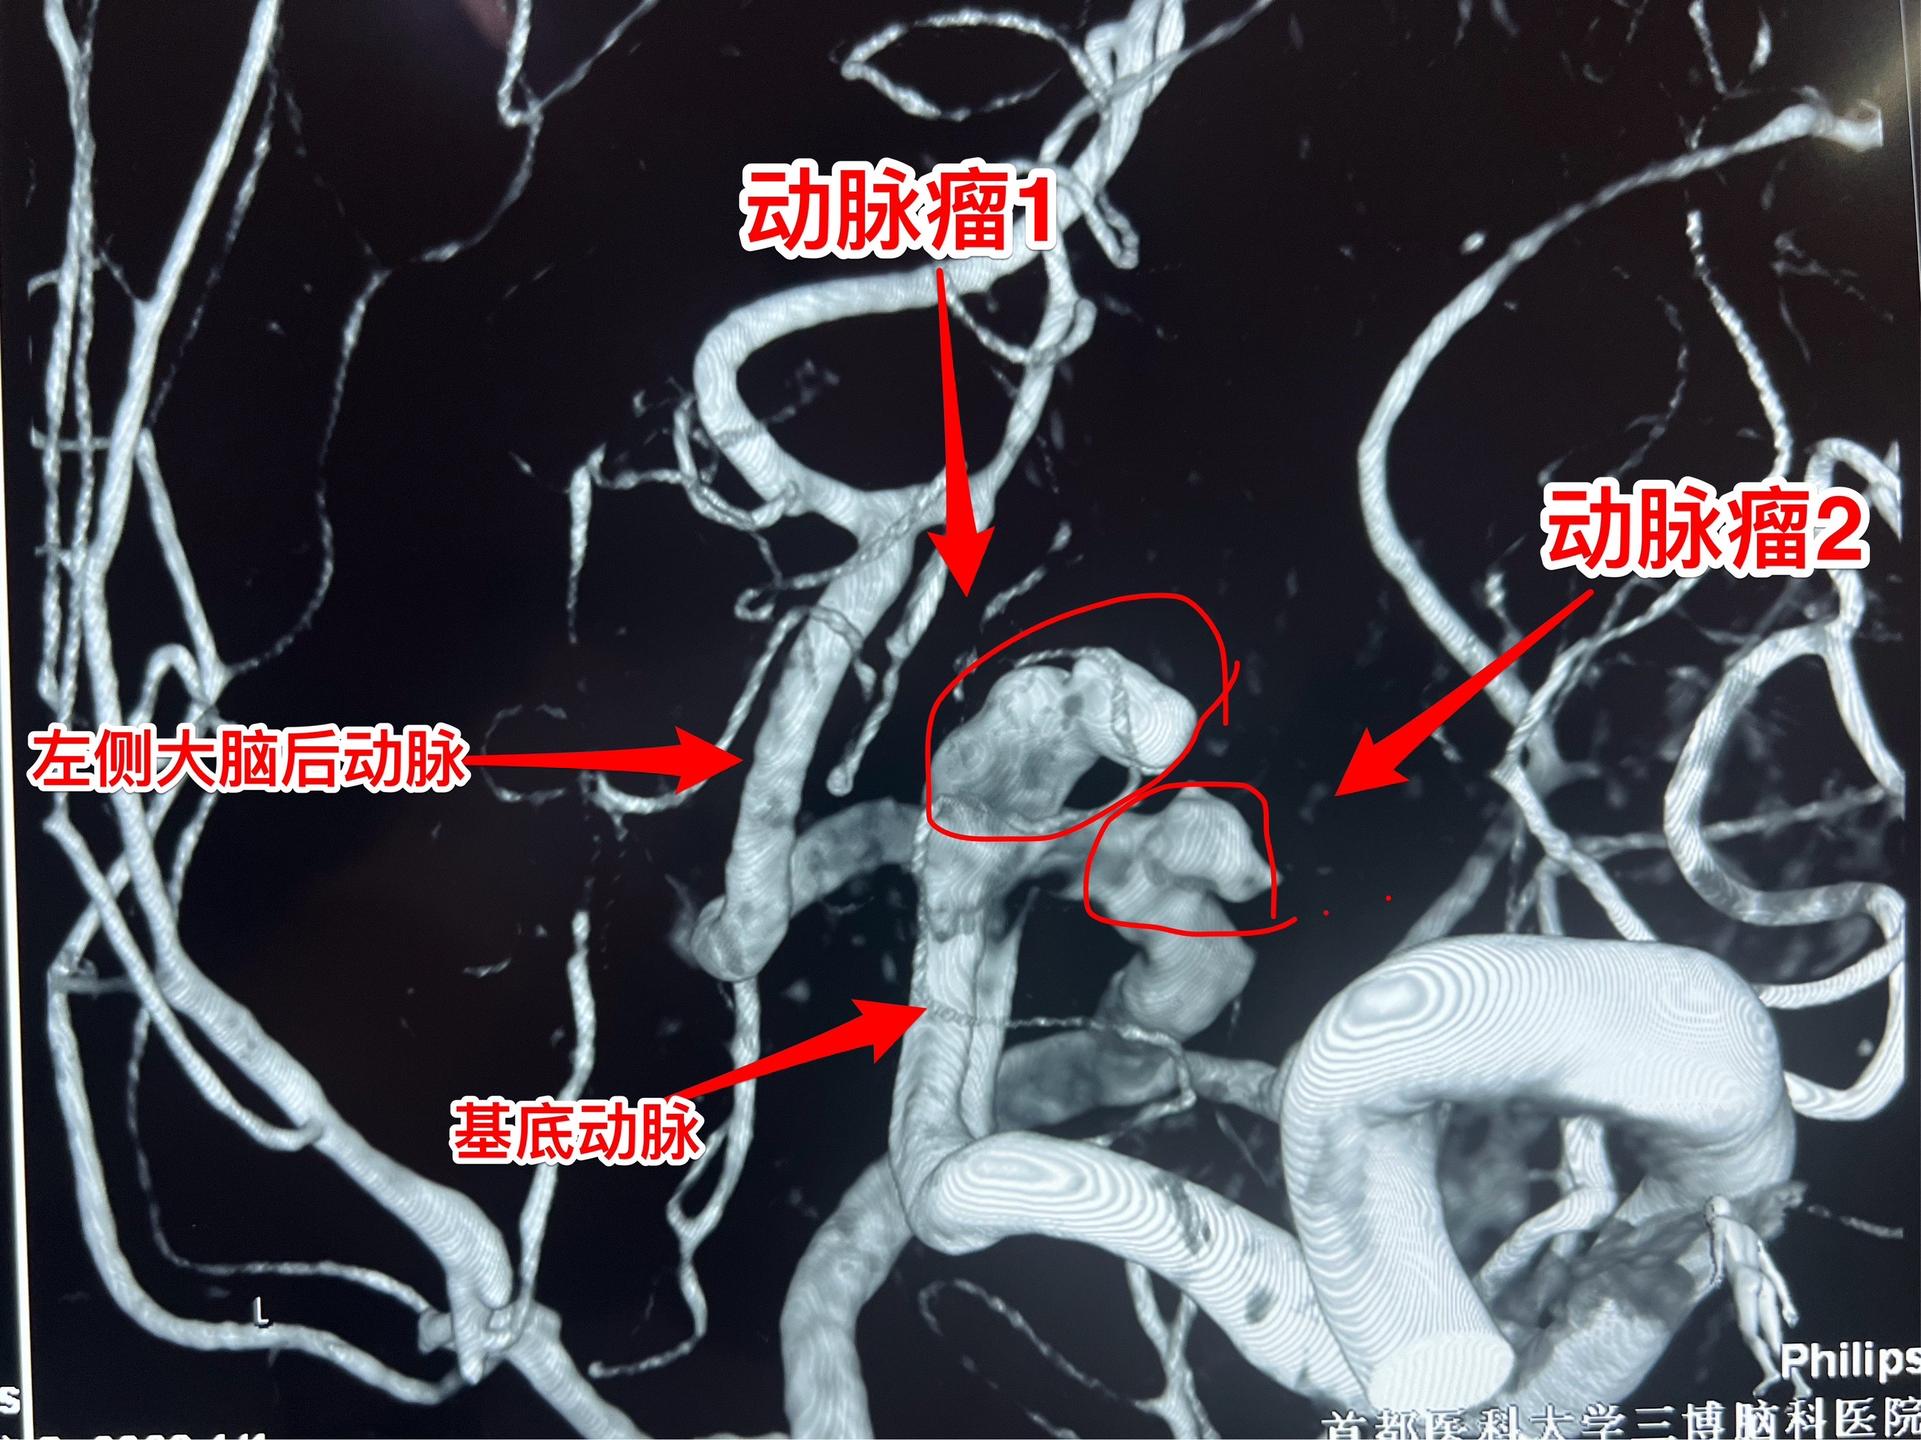

在烟雾病基础上合并后循环的动脉瘤。55岁佳木斯市女性,近三个月在北京生活。20多天前出现头晕、呕吐、全身疼痛不适,到医院行磁共振检查发现基底动脉和大脑后动脉的可疑动脉瘤,随后作了CTA检查,发现动脉瘤的确存在,而且两侧的颈内动脉不显影。 病人找我看病后,我向病人解释很有必要作一次脑血管造影术(DSA)。随即将病人收入院,作了脑血管造影术,结果见图。病人的双侧颈内动脉起始段几乎闭塞,脑底有烟雾状血管网形成,是典型的烟雾病。 由于双侧的颈内动脉几乎闭塞,导致双侧椎动脉代偿性的向前